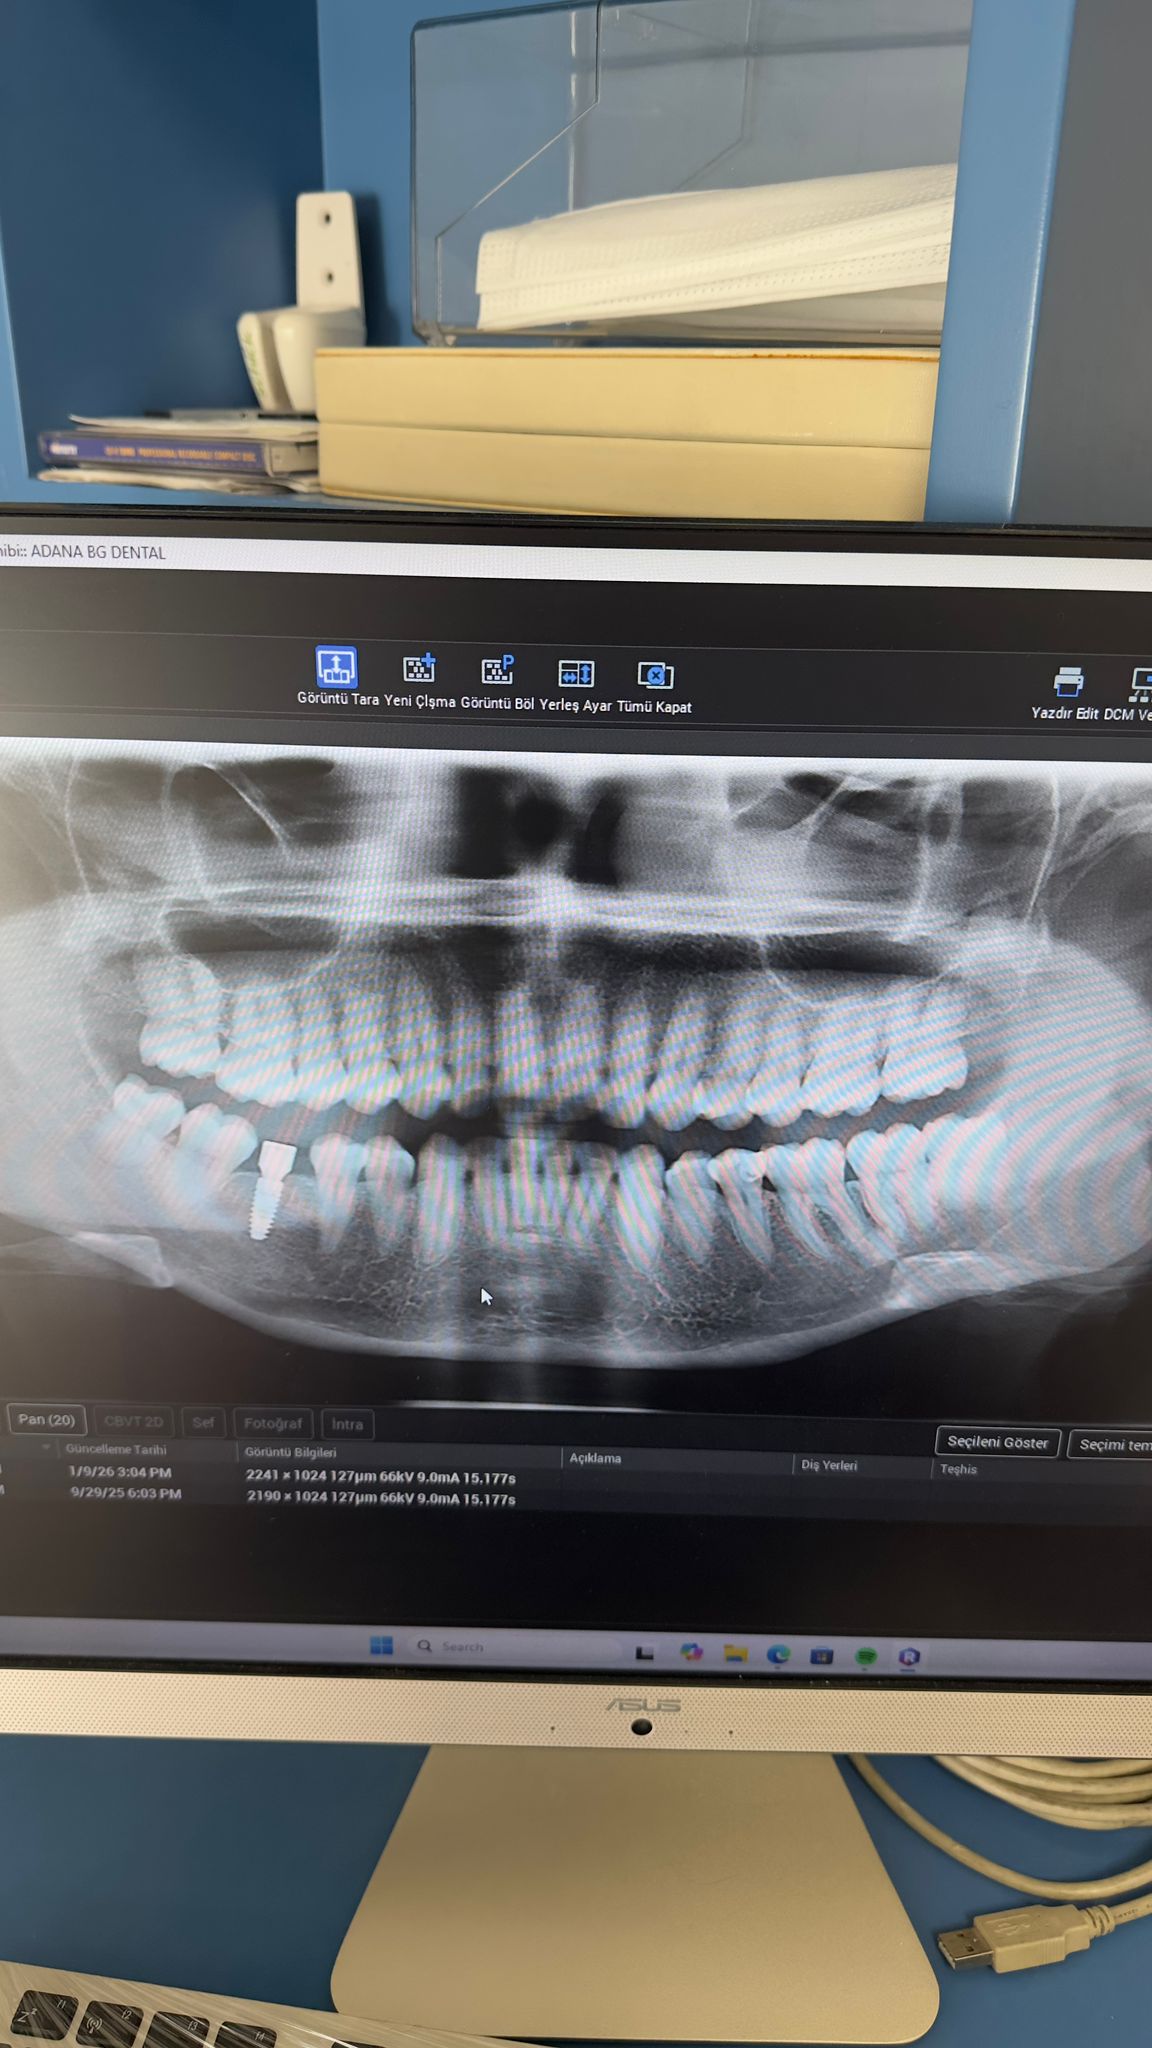

Ali Akıllıoğlu ( 01.09.1968) muayene edilip, panoramik film çekilmiştir. Alt ön bölgedeki 4 kesici dişinin sallandığı tespit edilmiştir. Kalp hastası olduğu için doktorundan lokal anestezi altında cerrahi işlem yapılabilmesi için görüş alınmıştır. Alt dört keser dişi çekilip , yan keserler bölgesine iki adt 3,2 mm çapında implant yerleştirilmiştir. Şimdi implantların osseintegrasyonu için beklenmektedir.3 Ekim 2025te muayene edildi. 07 Ocak 2026 da implantlar yerleştirildi.